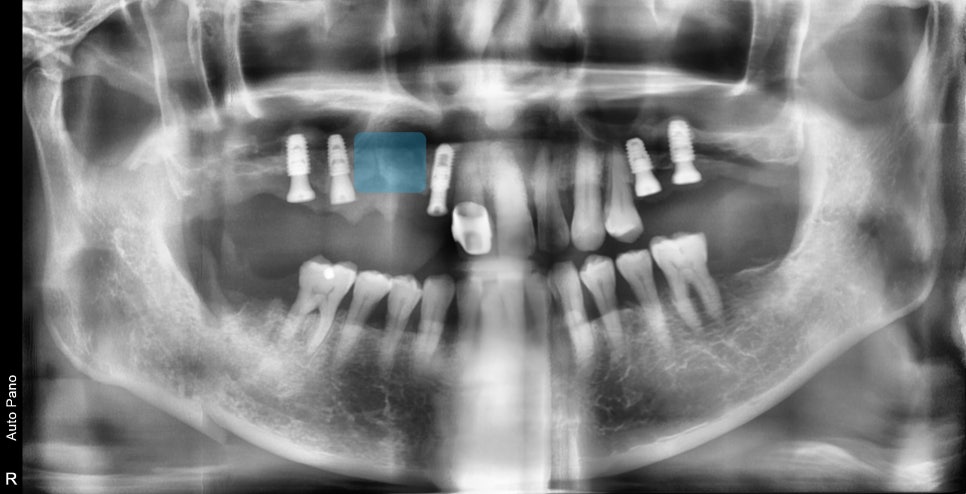

전반적으로 봤을 때 위턱뼈의 어금니 다수가 빠진 상태이고

남아있는 몇몇의 치아 주변에서 염증소견이 보입니다

3D CT를 찍은 진단 결과입니다

어금니 쪽의 뼈의 두께가 너무 얇아 임플란트 수술을 위해서는

부비동이라고 알고 있는 상악동 공간에 임플란트 지지 공간을 만들어줘야 합니다.

이것이 상악동 거상술이라는 추가적인 술식이 필요한 이유입니다.

중간쪽 가장 심한 치주염이 진행된 치아 부분입니다.

빨갛게 표시된 부분이 뼈가 있어야 수술이 가능하지만

뼈이식을 동반하더라도 즉시 수술은 불가능한 상태였습니다.

사진에 표시된 부분은 광범위한 염증으로 인해 즉시 임플란트 수술은 어려웠고